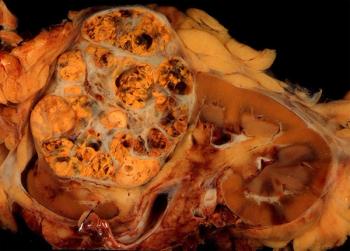

This slide show features various images of papillary, clear cell, chromophobe, and tubulocystic renal cell carcinoma.